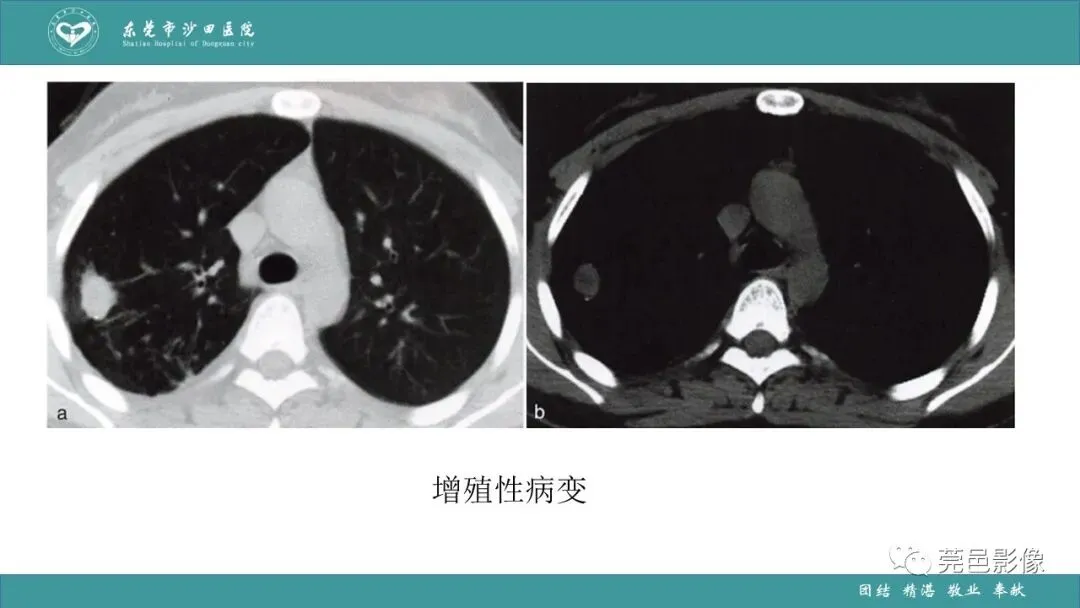

>课件 | 肺炎克雷伯杆菌肺炎影像学诊断与鉴别诊断

课件 | 肺炎克雷伯杆菌肺炎影像学诊断与鉴别诊断